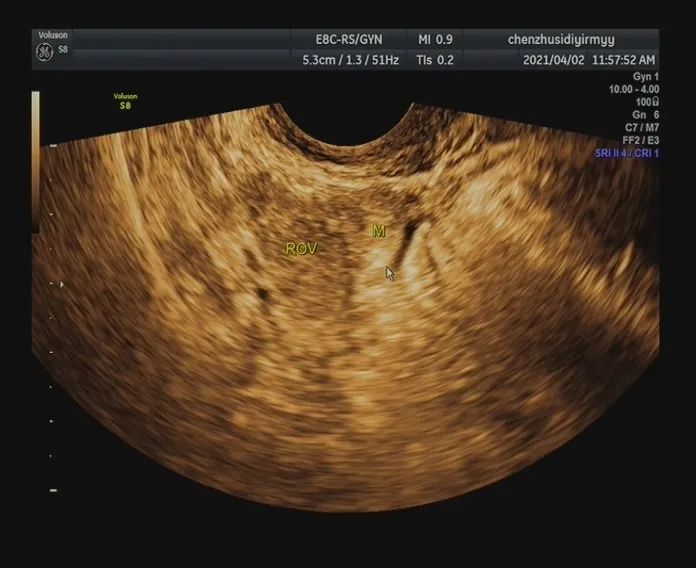

盆腔阴道彩超检查:子宫内未见明显异常回声团,左侧卵巢形态大小正常,右侧卵巢内可见一黄体声像,右侧附件区可见一大小约20mm×15mm的混合性包块,内可见一细小无回声区,包块周边可见少许血流信号。

盆腔可见深约27mm的液性无回声区,内透声差。

HCG显示阳性,子宫内未见妊娠囊,阴道彩超见右侧附件区混合性包块,考虑异位妊娠(输卵管型)。